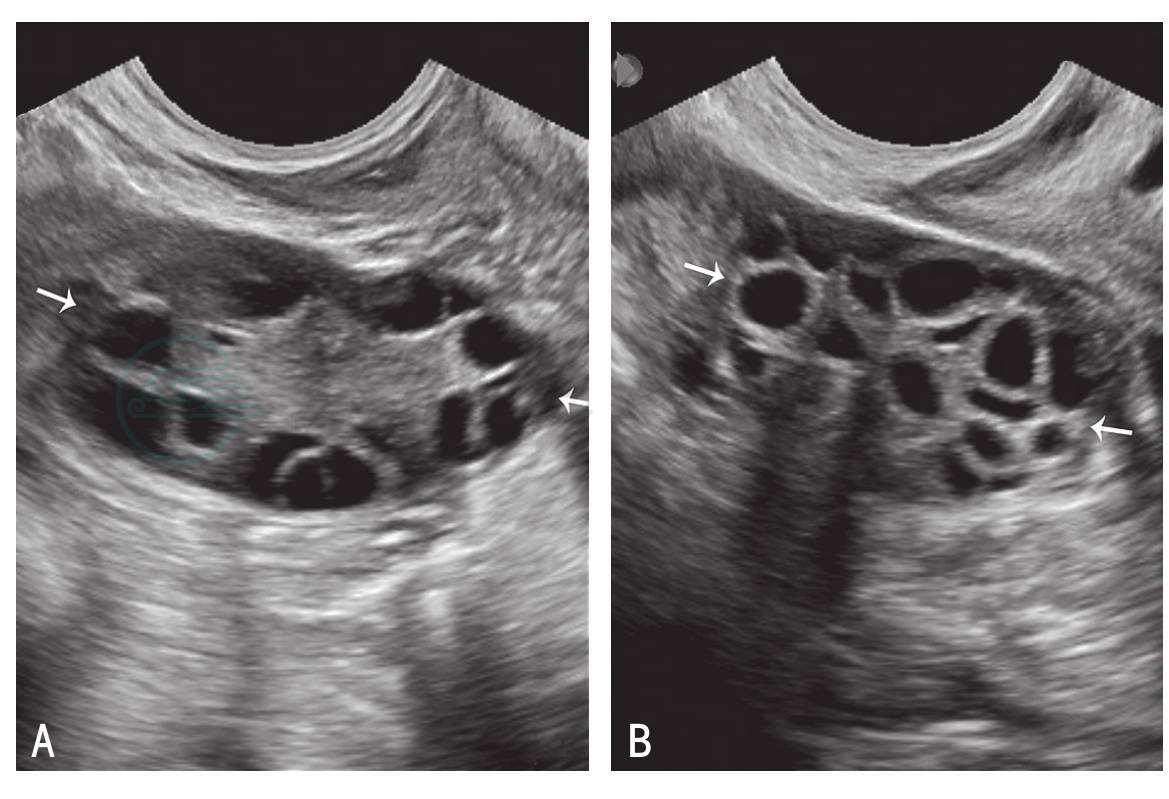

双侧卵巢轮廓清晰,均匀性增大,一侧或两侧卵巢内含有≥12个直径小于10mm的小囊泡状结构,在卵巢皮质呈车轮状分布;卵巢中部髓质回声增强;卵巢无优势卵泡生长及排卵征象(图7-3)。子宫大小正常或偏小,内膜薄,缺乏周期性变化,或内膜呈不同程度增生改变,无分泌期改变。

图7-3 卵巢多囊样改变声像

A.右侧卵巢多囊样改变声像;B.左侧卵巢多囊样改变声像;箭:卵巢